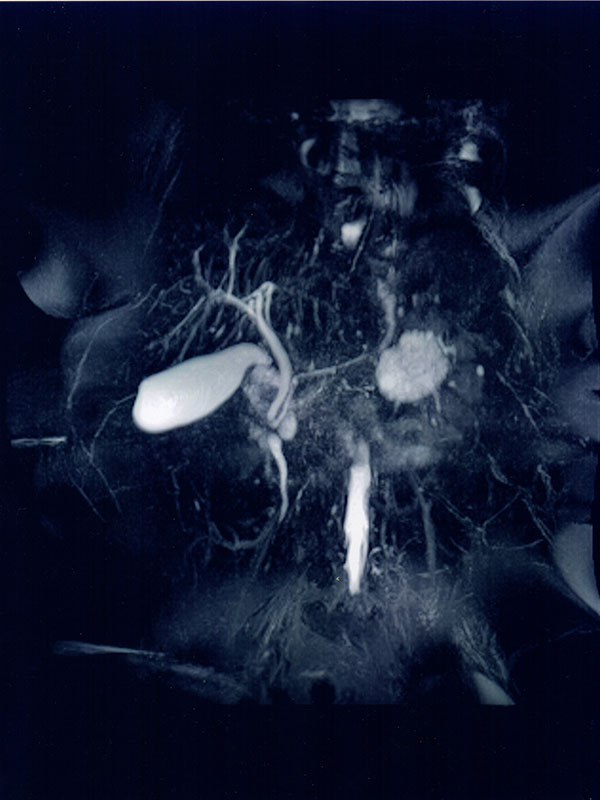

- Estudios vasculares, “Angio-resonancia” con medio de contraste.

- “Colangio-resonancia” estudio éste que permite analizar con detalle las vías biliares y sus enfermedades.

- Estudios de la vía urinaria o “Uro-resonancia”.